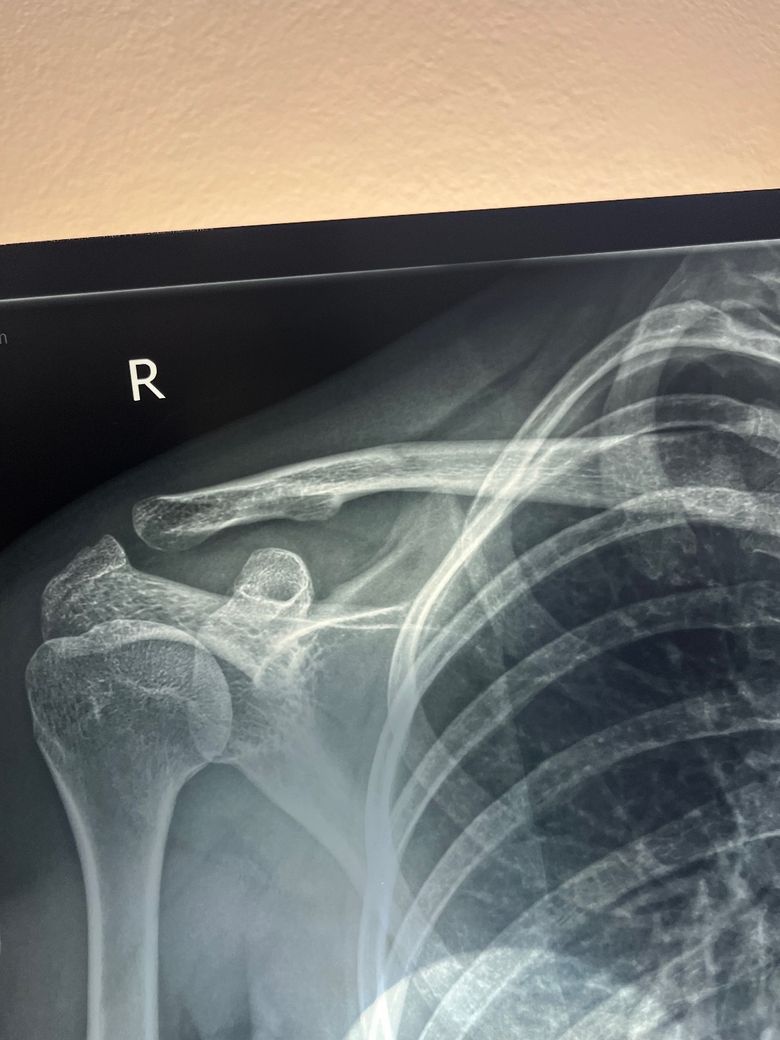

쇄골이 아픈데 엑스레이 상으로 짐작가시는 이유가 있을까요?

1월 말부터 오른쪽 쇄골이 아프기 시작했습니다. 지금은 초반보다는 통증이 덜하지만 여전히 쇄골쪽으로 무게가 가해지는 행동을 하면 다시 통증이 시작됩니다.

엑스레이와 씨티를 찍었더니 골절도 아니라고 하시는데 도대체 뭐가 문제일까요ㅠㅠ

CT Findings: A well-corticated linear oblique lucency through the right mid clavicle corresponds to a prominent nutrient foramen.

No clavicle fracture. Normal right-sided acromioclavicular and sternoclavicular joints.

Normal glenohumeral joint, proximal humerus and scapula.

The visualised chest and ribs are normal.

CT Conclusion: A well-corticated linear oblique lucency through the right mid clavicle corresponds to a prominent nutrient foramen.

• 1번 째 사진